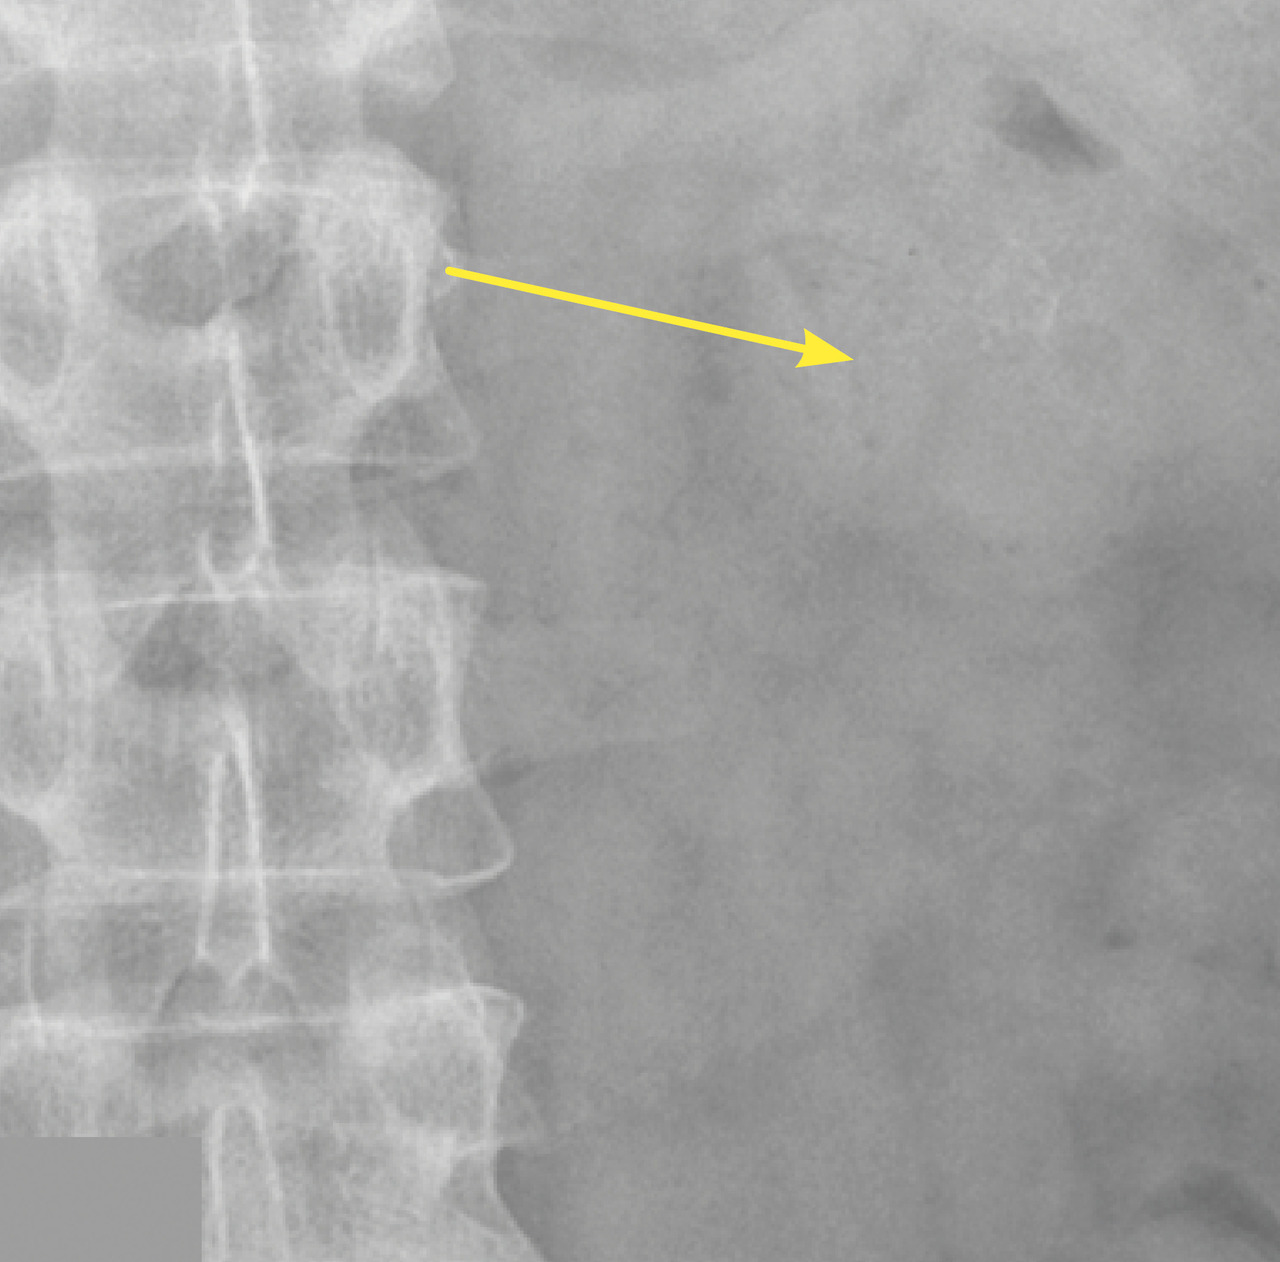

Lors de son hospitalisation, un scanner abdominal permet de localiser avec précision un calcul caliciel rénal radio-opaque gauche de 6 × 8 mm, de faible densité (354 UH), sans dilatation calicielle (fig. 1). En corrélation avec la lecture du scanner, le pourtour du calcul est difficilement visualisé sur la radiographie de l’abdomen sans préparation (fig. 2).

En raison de la taille du calcul, qui expose à un risque de migration symptomatique urétérale, l’ablation urétéroscopique est décidée et réalisée de manière élective une fois le traitement anticoagulant de l’embolie pulmonaire terminé. L’intervention se déroule sans complication (lithotripsie au laser in situ et extraction du calcul) [fig. 3]. Le patient est rentré chez lui vingt-quatre heures heures plus tard.